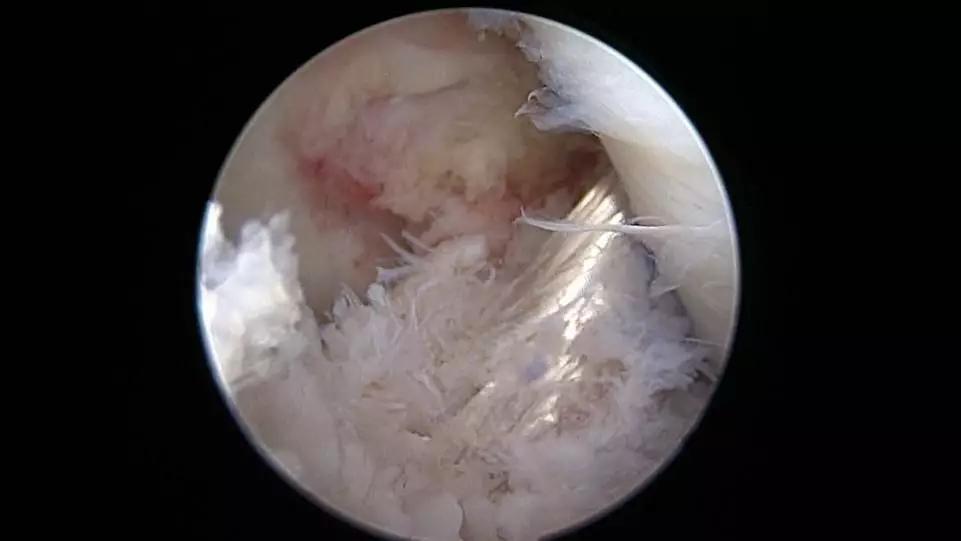

关节镜下探查见左膝前交叉韧带断裂

关节镜下探查见左膝关节前交叉韧带断裂,膝关节前叉韧带断裂诊断明确,决定取自体肌腱(股薄肌、半腱肌肌腱)于关节镜下行左膝关节前交叉韧带重建。

重建后的前叉韧带张力良好